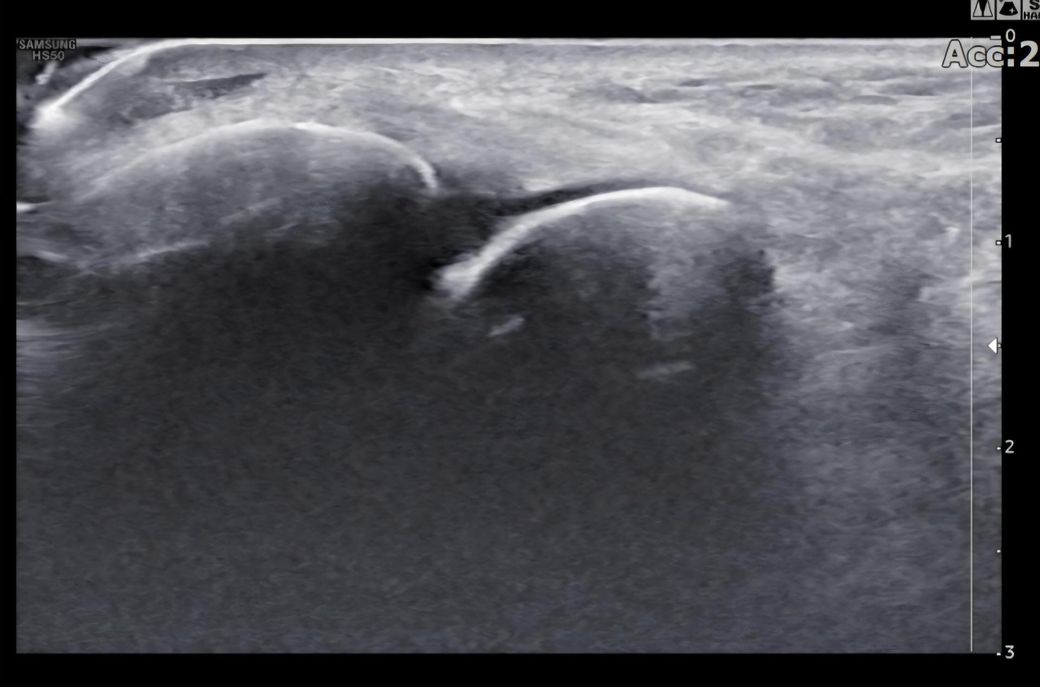

발목인대 상태 질문드립니다. (mri사진 첨부)

그런데 다친 지 2주 뒤부터 발목이 쑤시듯 아파 병원에서 초음파 검사를 했고, 전거비인대(ATFL) 2도 염좌 진단을 받았습니다. 이후 약 6주 동안 주 1회씩 충격파, 물리치료, 도수치료 등을 받았습니다. (고정치료는 시기가 늦었다며 진행하지 않았습니다.)

그래도 통증이 남아 8월 5일에 MRI를 촬영했는데, 병원에서는 “인대는 이어져 있고, 이 정도면 재활운동으로 호전될 것”이라는 설명을 들었습니다.

그리고, 처음 초음파 사진(6월 촬영)과 비교하여

mri 사진(8월 촬영)상 인대가 호전됬는지도

알고 싶습니다.

올려주신 mri를 보면 전거비인대는 연속성이 유지되고 있고 파열이나 큰 손상 흔적은 없어 재활로 회복 가능한 상태로 보입니다 다만 3개월 가까이 활동 시 통증과 미열감이 남아 있는 것은 조직 회복이 아직 완전히 끝나지 않았거나 주변 연부조직 관절 움직임 제한 등으로 인한 과민 반응일 수 있습니다.

초음파와 비교하면 mri 상으로 인대 연속성이 확인되므로 심각한 악화나 재파열은 아닌 것으로 판단됩니다